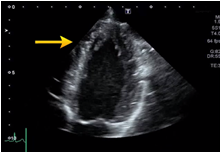

Adjustment of the observation depth

The observation depth is used to adjust the depth from the body surface to be displayed as an image on the monitor. When you observe the posterior part of the heart, for example, pleural effusion and descending thoracic aorta aneurysm, increase the observation depth (deeper). But increasing the depth may allow lower frame rates.